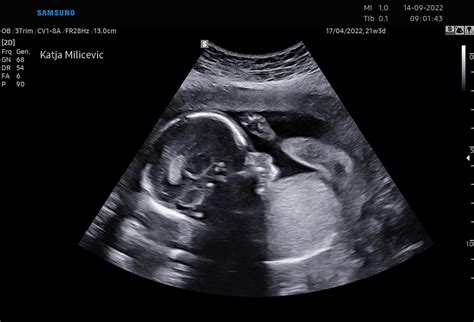

V 10. tednu nosečnosti je vaš malček že dosegel velikost kumkvata. Čeprav je še vedno majhen, meri približno 3 do 4 centimetre v dolžino in tehta okoli 4-5 gramov, je njegova notranja zgradba že izjemno kompleksna. Ključni razvojni mejnik tega tedna je dokončana strukturna oblika srca s štirimi votlinami, ki sedaj bije s hitrostjo med 140 in 170 utripi na minuto. Ta močan srčni utrip je že mogoče zaznati z ročnim Dopplerjem, kar je za marsikatero nosečnico prvi otipljiv dokaz življenja v njej.

Prsti na rokah in nogah, ki so bili prej povezani s tanko kožico, so sedaj popolnoma ločeni, saj je proces programirane celične smrti (apoptoze) uspešno razgradil tkivo med njimi. Na konicah prstov se že oblikujejo zasnove nohtov. Repu podobna struktura, ki je bila prisotna v prejšnjih tednih, je izginila. Čelo je zaradi hitrega razvoja možganov videti izrazito napihnjeno in visoko nameščeno na glavi. Veke se spustijo nad oči, kar jih ščiti pred amnijsko tekočino. Skozi prosojno kožo je mogoče opaziti obris hrbtenice. Noge so že precej dolge, roke pa so na zapestjih upognjene in se nahajajo nad srcem.

Če še niste, je 10. teden nosečnosti primeren čas, da se pogovorite z zdravnikom o presejalnih testih, kot je kombinirani test (nuhalna svetlina in krvni test), ki se običajno opravi med 11. in 14. tednom. Ti testi niso obvezni, vendar lahko pomagajo pri zgodnjem odkrivanju morebitnih kromosomskih nepravilnosti.